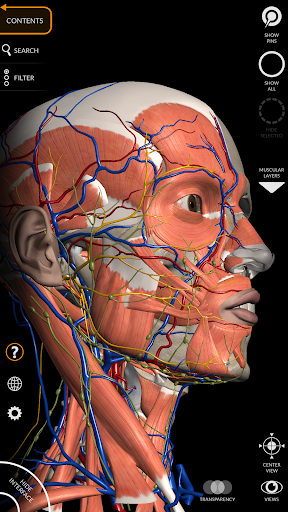

"Anatomy 3D Atlas" cho phép bạn nghiên cứu giải phẫu người theo cách dễ dàng và tương tác.

Thông qua giao diện đơn giản và trực quan, bạn có thể quan sát mọi cấu trúc giải phẫu từ mọi góc độ.

Các mô hình giải phẫu 3D đặc biệt chi tiết và có kết cấu lên đến độ phân giải 4k.

Việc phân chia theo vùng và chế độ xem được xác định trước giúp quan sát và nghiên cứu các bộ phận hoặc nhóm hệ thống riêng lẻ và mối quan hệ giữa các cơ quan khác nhau.

• Hệ thống cơ xương

• Hệ thống tim mạch

• Hệ thống thần kinh

• Bộ lọc để ẩn hoặc hiển thị từng hệ thống

• Hình dung các cơ qua các lớp từ lớp nông đến lớp sâu nhất